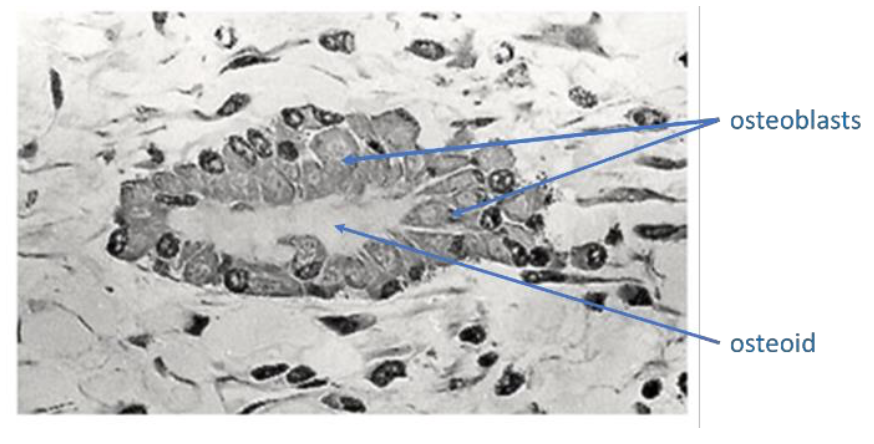

What do osteoblasts do?

Synthesise new bone, deposit osteoid

What is osteoid?

Matrix protein of bone: collagen, osteocalcin, osteopontin

Fill in the missing labels: